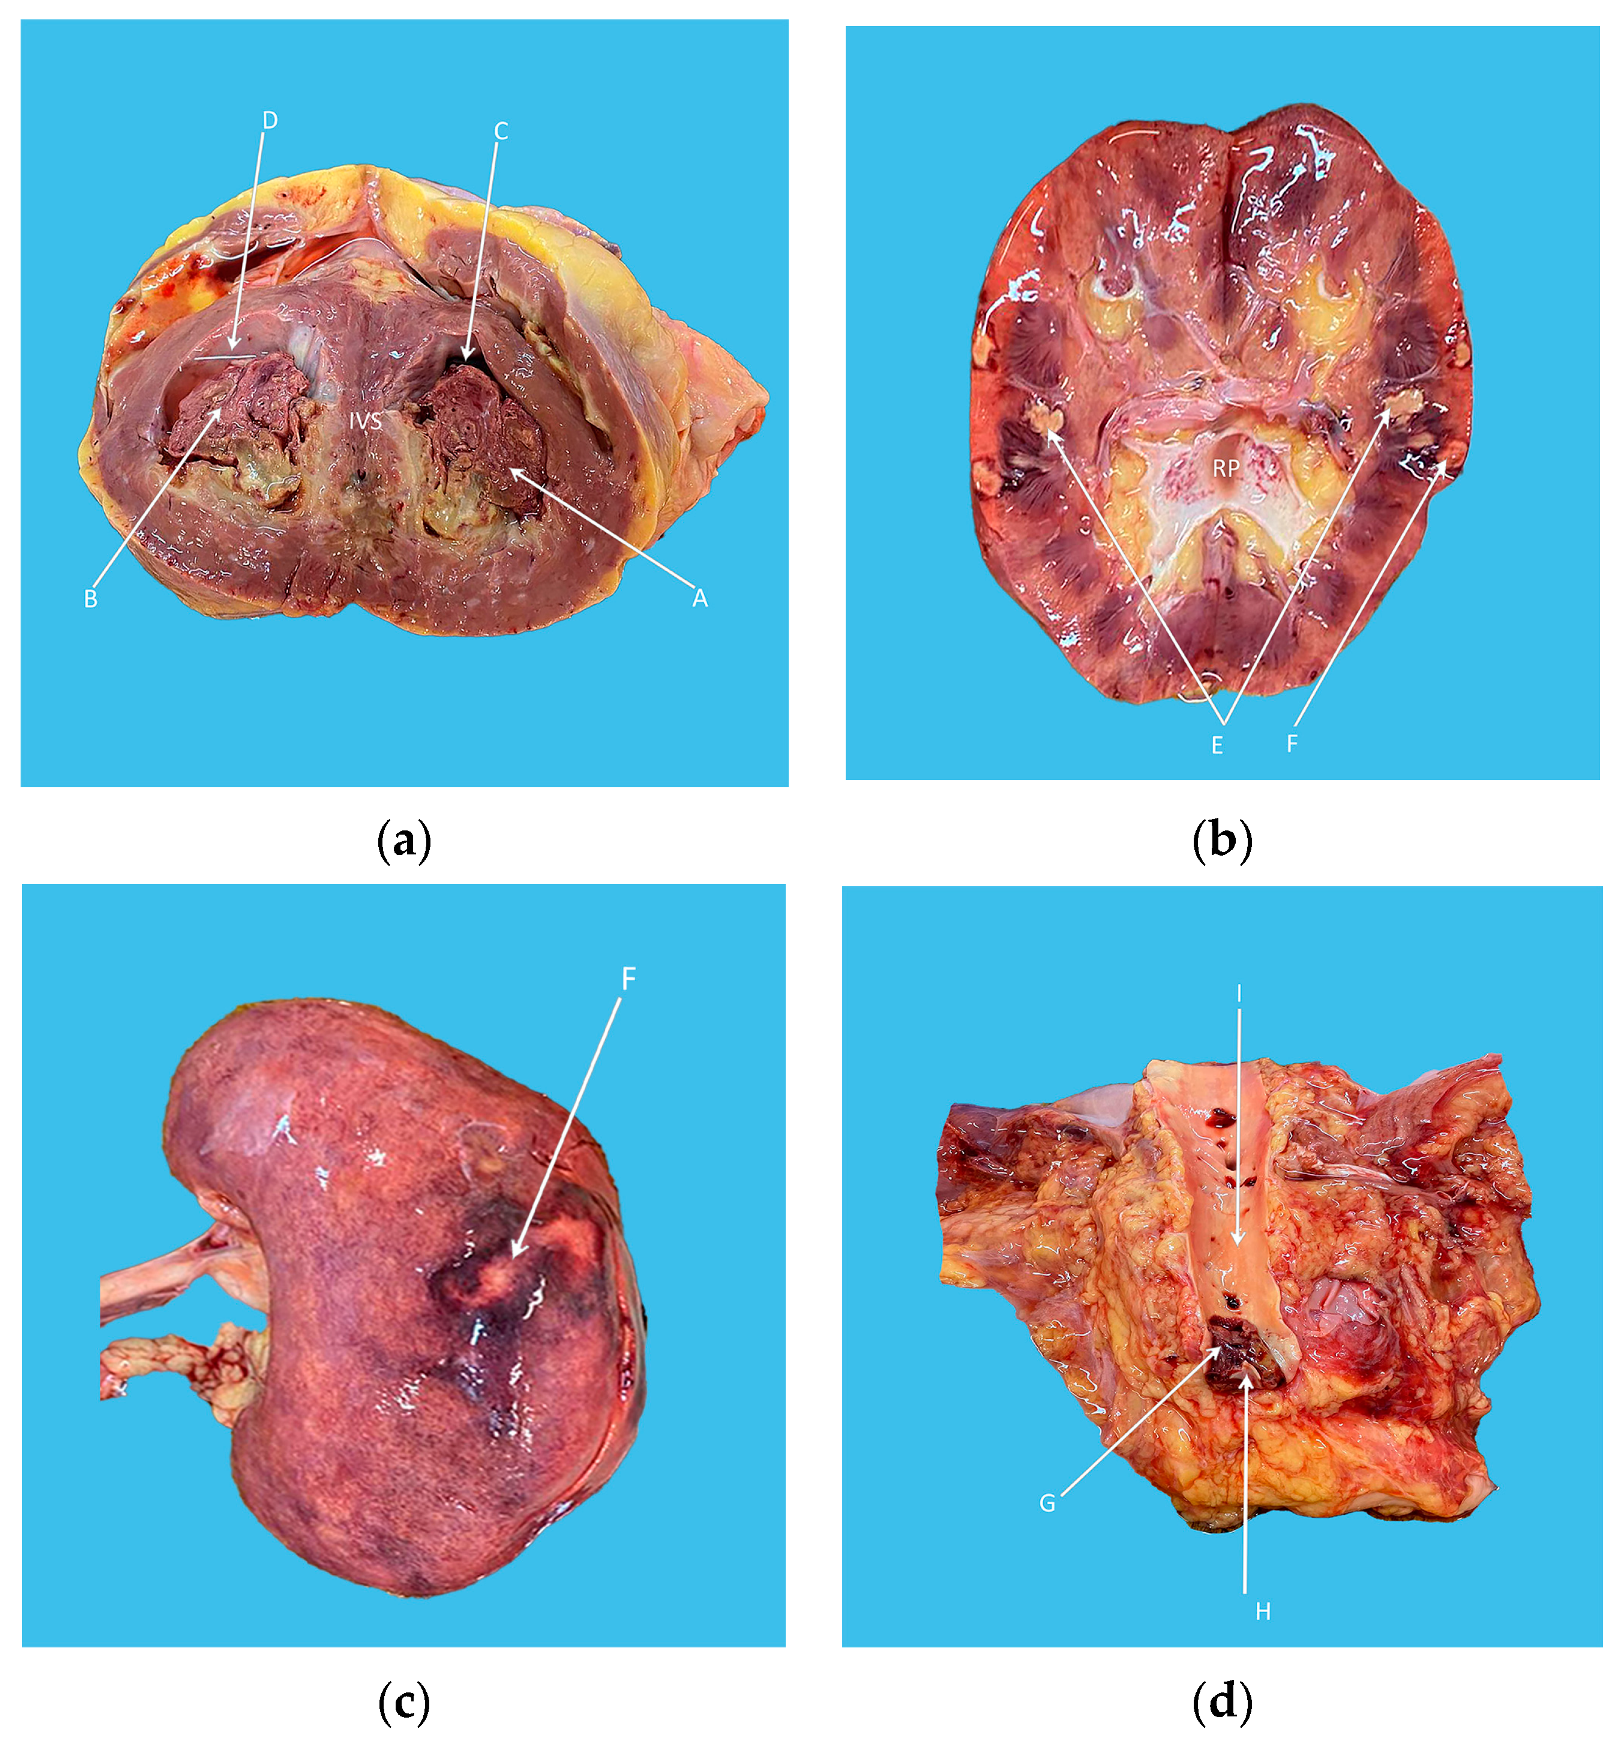

2. Case Presentation

3. Discussion